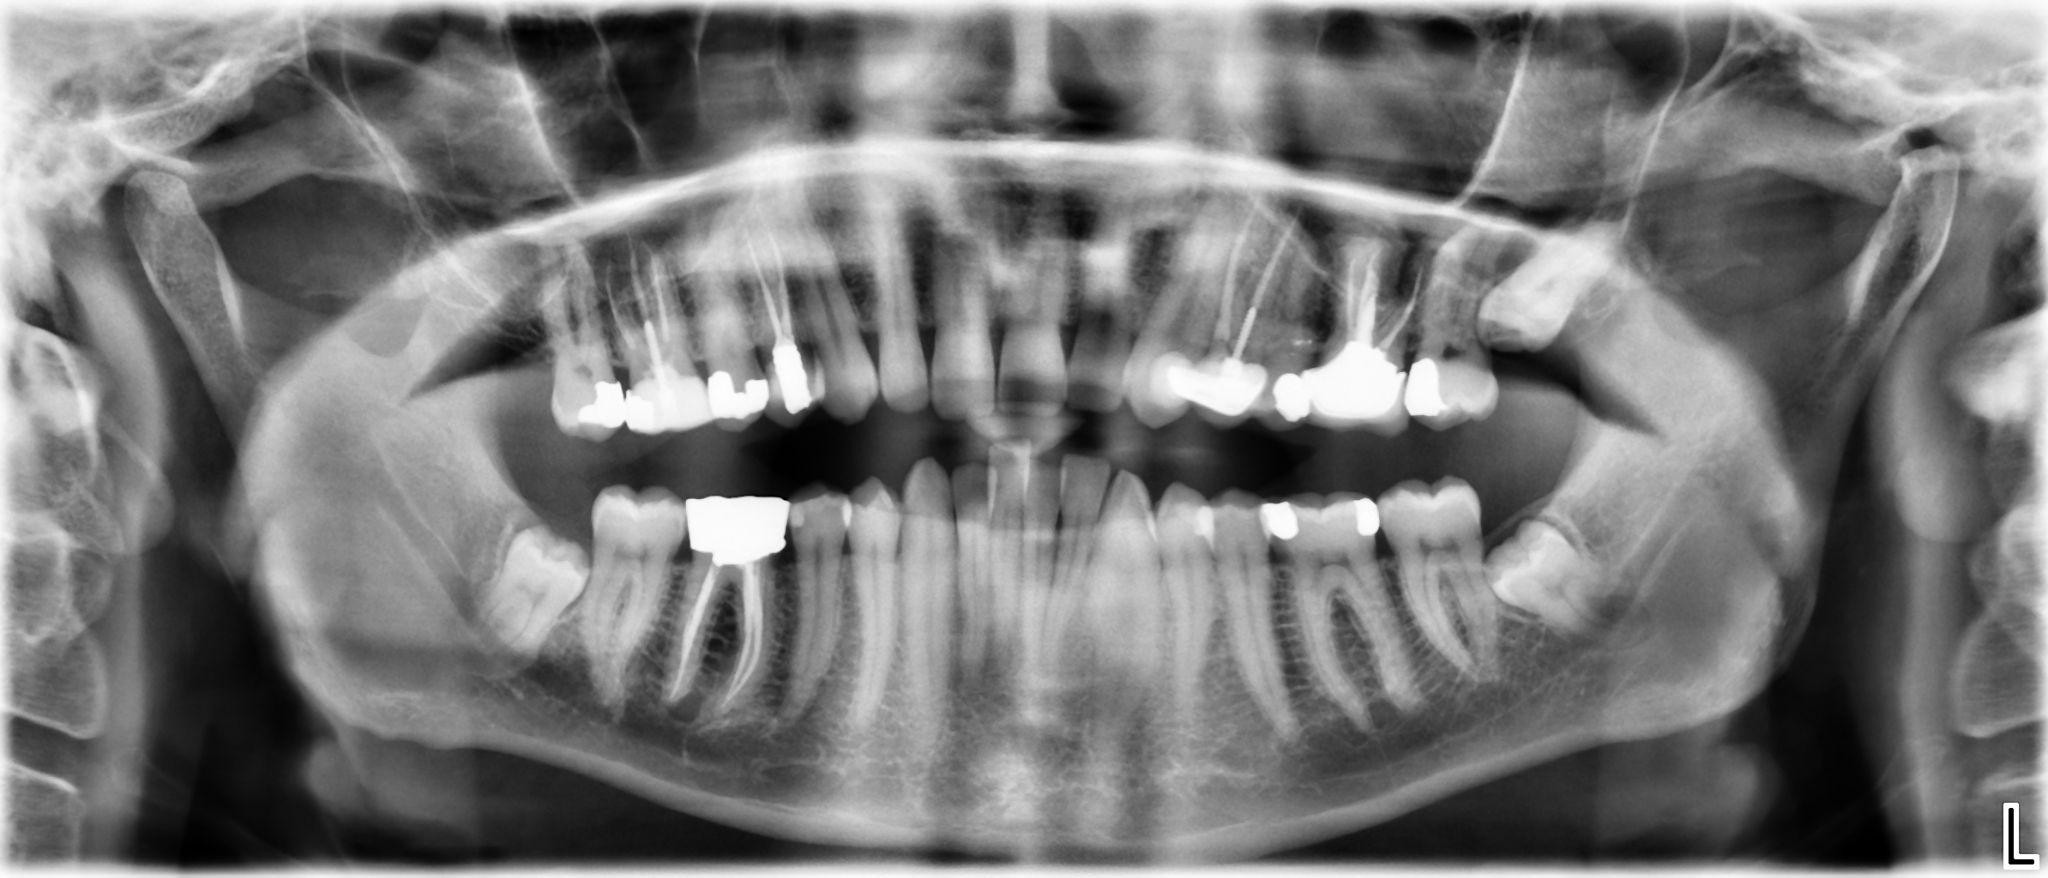

5. What options can be selected for the first quadrant of this panoramic X ray?

6 / 24

6. What options can be selected for the second quadrant of this panoramic X ray?

7 / 24

7. What options can be selected for the third quadrant of this panoramic X ray?

8 / 24

8. What options can be selected for the forth quadrant of this panoramic X ray?